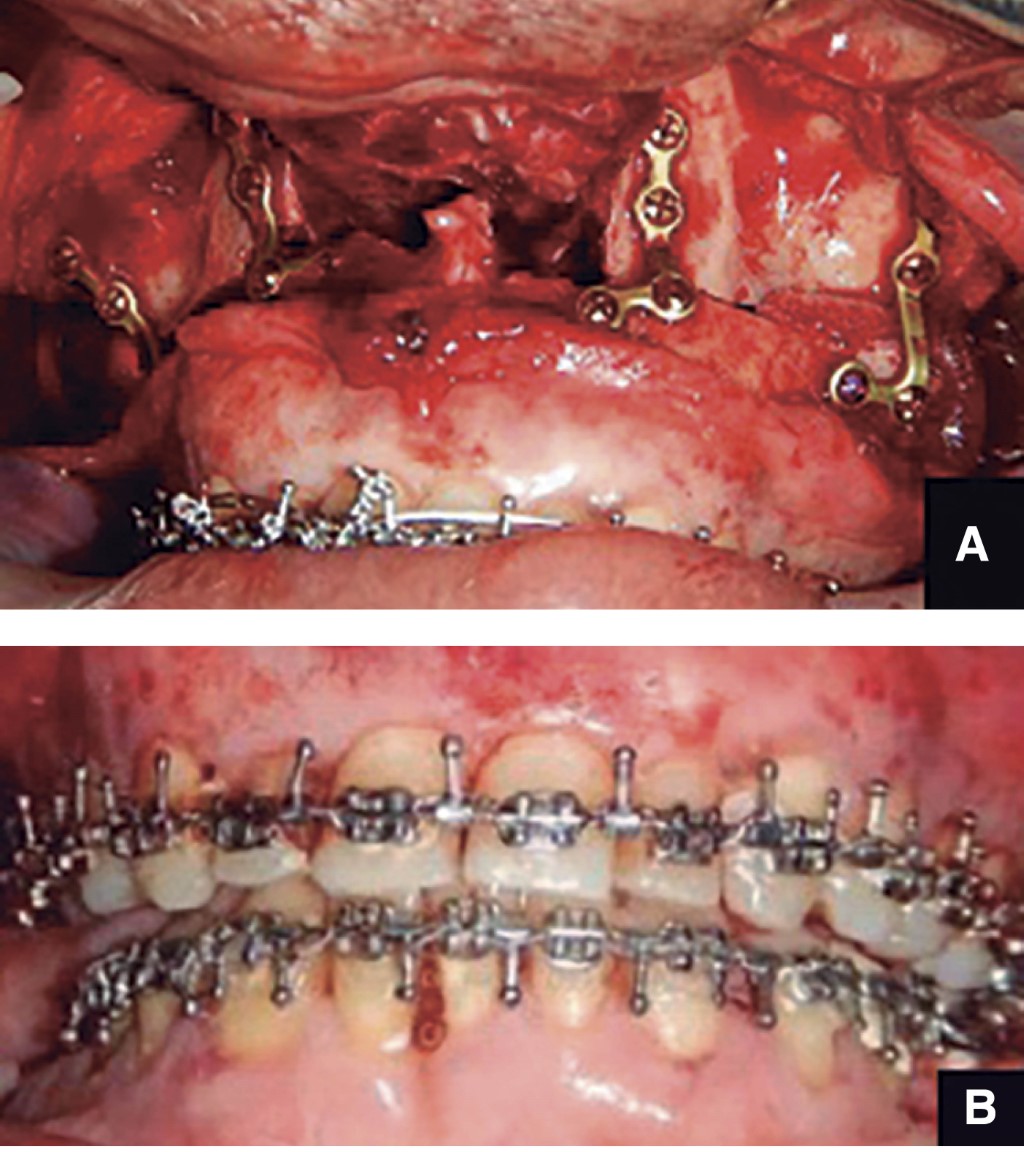

• 10. Osteotomía Le Fort I.

• 11. Cierre de abordaje intraoral.

• 6. FIM con férula intermedia en cavidad oral, se aísla nuevamente la cavidad oral con el Tegaderm.

• 7. Cambio de guantes y colocación de nuevos campos quirúrgicos para adaptar la prótesis articular bilateralmente.

• 8. Colocación de injerto de grasa suprapúbica autóloga sobre las prótesis.

• 9. Cierre de abordajes.